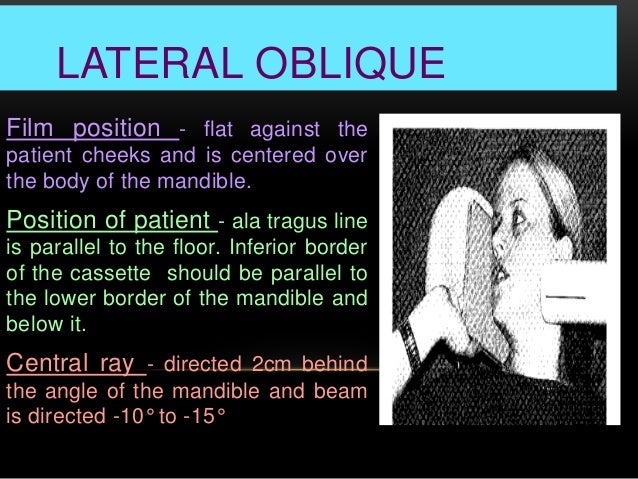

Tragus of the ear must be aligned with the plastic guides ala tragus line should be 50 from level positioning the patient position the patient panoramic lead apron must be used position apron high in front to protect the thyroid apron should be lower in back to expose the neck. Discussion most panoramic x ray machines use the ala tragus line for patient positioning whereas a few use the orbito meatal line. Ala tragus line is one of the common extra oral soft tissue land mark utilized in dental clinics for occlusal plane orientation. Here the occlusal plane should be mildly curved upward to make a smile like line.

The angle between this line and the horizontal plane is 3on the panorex and 4on the. Focal trough layer that area between the x ray source and the image receptor that will be imaged distinctly on the panoramic. In other words the ala of the nose should be slightly inferior to the height of the tragus. These zones are as follows.

Important in determining the correct position of the patient s head. Exposure was 80 to 90 kv at 10 ma for 1 5 to 2 seconds in accordance with the subject s physical. The panorex i s. To achieve the correct vertical angulation the head must be positioned upright and symmetrical with the ala of the nose just inferior to the height of the tragus.